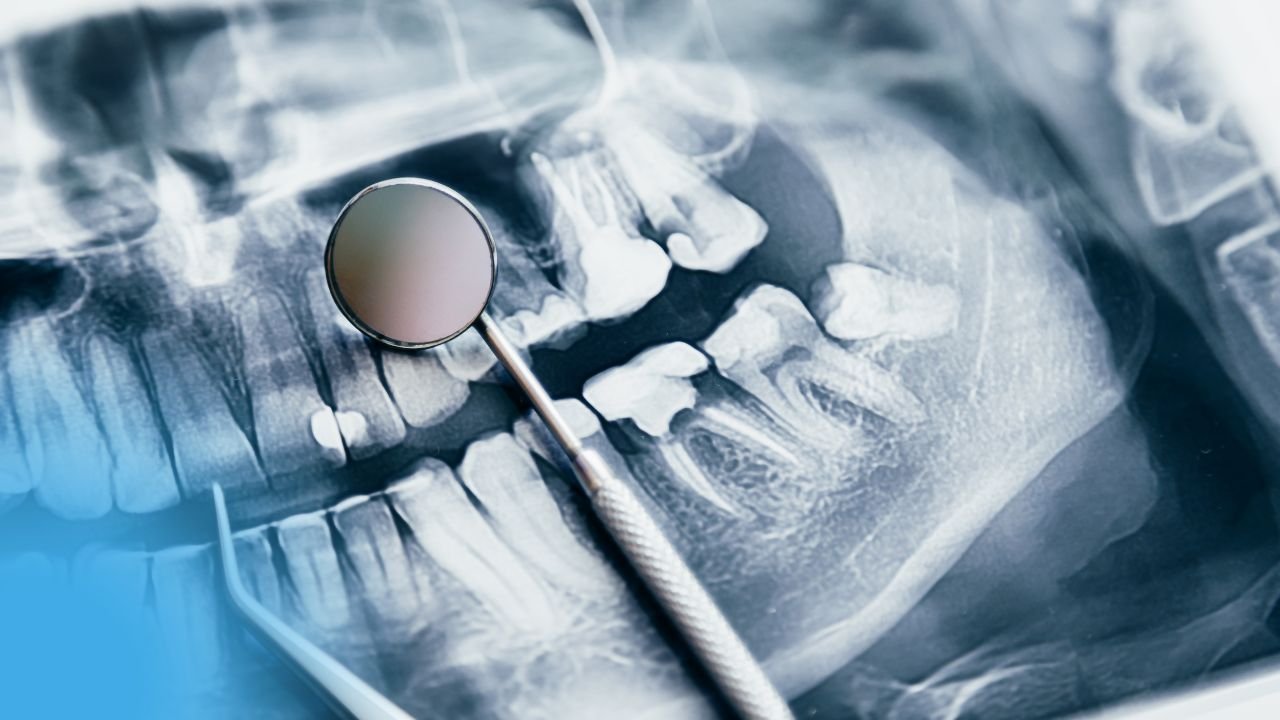

Interprétation de la panoramique dentaire

Qualité de la radio :

Il s’agit d’une radio panoramique de mauvaise qualité par présence d’artéfacts et certaines structures ne sont pas visibles (telles que les échancrures sigmoïdes, la partie postérieure du condyle droit, la cavité glénoïde droite et l’apophyse coronoïde droite). Il y a un dédoublement de l’apophyse coronoïde gauche.

État des bases osseuses :

Continuité des bases osseuses sans image pathologique.

État des ATM :

ATM droite non visible, ATM gauche symétrique et centrée dans sa cavité glénoïde.

La formule dentaire :

Les structures radio-opaques au niveau des couronnes correspondent à des brackets orthodontiques.

Quadrant supérieur droit

- Présence des dents : Toutes sauf 18.

- Points de contact : Contact serré entre 11-12, 12-13, 13-14, 14-15, 15-16, 16-17.

- État des couronnes :

- Image radio-opaque au niveau de la 11 (distal) et la 12 (couronnée) correspondant à des restaurations coronaires.

- Image radio-claire au niveau de la 12 correspondant à une carie secondaire.

- Carie du côté mésial de la 13.

- État des racines :

- Racine divergente du côté mésial de la 11.

- Racine droite et robuste de la 13.

- Racines divergentes de la 16.

- Racines convergentes de la 17.

- État des tissus parodontaux :

- Élargissement de l’espace desmodontal (détectable sur la 11 et la 13).

- La lamina dura entre la 11 et la 12 est visible et apparaît continue sans rupture.

- Absence de lyses osseuses.

- Trabéculations osseuses lâches.

Quadrant supérieur gauche

- Présence des dents : Toutes sauf 26, 27, 28.

- Points de contact : Point de contact serré entre la 23 et 24, 24 et 25.

- Restaurations coronaires au niveau de la 21 (distal) et la 22 (mésial).

- Carie du côté distal de la 22.

- Racine robuste et déviée distalement de la 23.

- Racine déviée mésialement de la 24.

- Élargissement de l’espace parodontal détectable sur la 21.

- La lamina dura n’est visible qu’au niveau des dents antérieures et elle apparaît continue sans rupture.

Quadrant inférieur gauche

- Présence des dents : Toutes sauf 37, 38.

- État des couronnes et des racines :

- Carie du côté distal de la 36.

- Restaurations coronaires au niveau de la 36.

- Racine distale de la 35.

- Racine mésiale coudée de la 36.

- Élargissement de l’espace parodontal au niveau de la 33.

- La lamina dura visible de la 33 à la 36.

- Absence de lyse osseuse.

Quadrant inférieur droit

- Présence des dents : Toutes sauf 46, 48.

- Points de contact : Point de contact serré entre la 42 et 43, 44 et 45.

- Restaurations coronaires au niveau de la 47.

- Élargissement de l’espace desmodontal détectable en distale de la 45.

- La lamina dura est visible sur la 45 et la 47.

NB : Les racines des quatre incisives inférieures apparaissent courtes, ce qui est dû au mouvement de torque effectué par le praticien afin de les vestibuler.